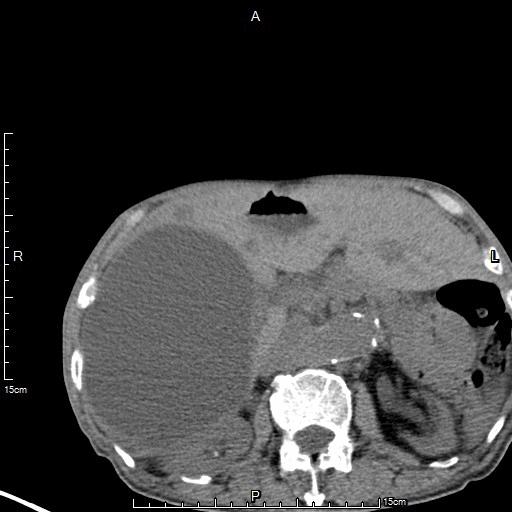

肝囊肿引流及硬化治疗后复查,囊肿明显缩小